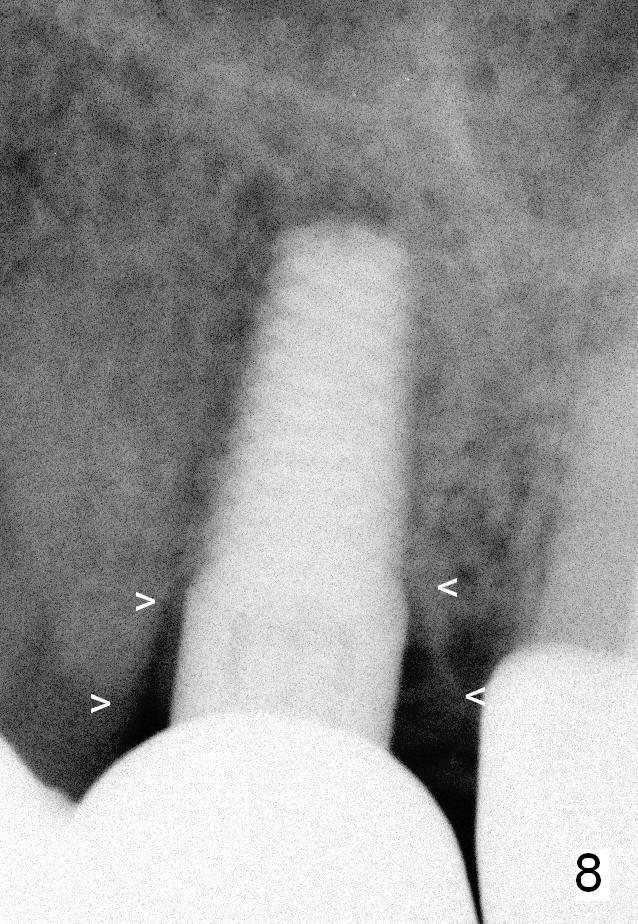

A 45-year-old lady is nervous about dental treatment. The missing tooth #13 was replaced by a 3-unit bridge. The latter is sectioned because the posterior abutment has caries. PA in Fig.1 is taken when root canal therapy and build up are finished. Fig.2 shows the wide edentulous area with a single-unit crown being tried in for #14. Osteotomy is initiated with the crown in place without cementation, since it is easy to determine the mesiodistal position (Fig.3 red lines). Without the crown in place, osteotomy tends to be distal. In this case, the osteotomy is later attempted to be moved distally with Lindamann bur and deepened to 14 mm from the gingival margin (Fig.4). A 2.5 mm reamer is being used at 50 RPM to increase osteotomy with difficulty. Drills have to used at high RPM instead (Fig.5 4x14 mm). A 4.5x14 mm tissue-level implant is placed with insertion torque >60 Ncm (Fig.6 I); a 4x3 mm abutment (A) is placed immediately for an immediate provisional. Fig.7 is taken 7 days postop to show the gingival recipient site formed by the provisional. The patient is so afraid of X-ray that the next one is taken 1.5 years post cementation (Fig.8). It appears that dense bone bundle forms between the crest and the 1st implant thread (adaptation functional change, arrowheads). The bone density continues to increase 2 years 8 months post cementation (Fig.9 *, 10); the bone has grown into the area between the 1st 2 threads (arrow).